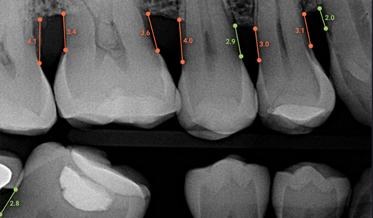

Using Three Familiar Radiographic Shapes to Improve Dental Implant Longevity